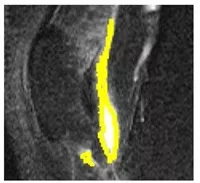

Effusion-Synovitis Volume Description:

We have a customized semi-automatic software to measure knee effusion-synovitis volume.

around 10 min/knee MRI.

Intra-tester (ICC [3,1] = 0.87)

Inter-tester (ICC [2,1] = 0.91)

Effusion